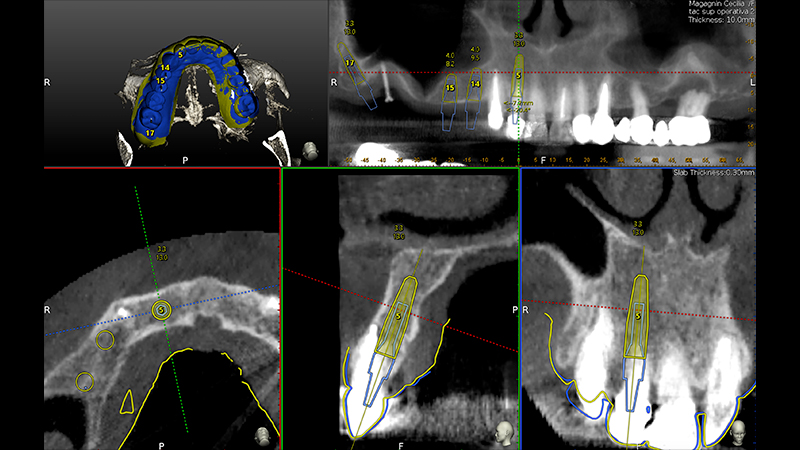

Veniva eseguita la pianificazione del caso con l'utilizzo dell'STL della Biocopia (Fig. 9) e della gengiva guarita (Fig. 10), e di tutti gli impianti: zona 12 con pianificazione post-estrattiva flapless con Socket Shield (Fig. 11), zona 14 (Fig. 12), zona 15 (Fig. 13) e zona pterigoidea (Fig. 14). Dopo la chirurgia (Video 1 e 2), OPT post-operatoria e endorali venivano fatte per valutare il rialzo di seno trans-crestale (Figs. 15, 16, 17, 18).

Pianificazione chirurgica della posizione implantare

Fig. 9 - Pianificazione chirurgica della posizione implantare su Software Navident (Claronav) basandosi sulla posizione dei denti originali mediante sovrapposizione di impronta ottica con e senza i denti (STL). Particolare attenzione è stata posta al parallelismo degli impianti 15 e 14, al corretto posizionamento con tecnica Socket Shield su 12 e alla correzione predefinita di 30° del moncone dell'impianto pterigoideo per mantenere il parallelismo conometrico protesico

Pianificazione chirurgica della posizione implantare su Software Navident

Fig. 10 - Pianificazione chirurgica della posizione implantare su Software Navident (Claronav) basandosi sulla posizione dei denti originali mediante sovrapposizione di impronta ottica con e senza i denti (STL). Particolare attenzione è stata posta al parallelismo degli impianti 15 e 14, al corretto posizionamento con tecnica Socket Shield su 12 e alla correzione predefinita di 30° del moncone dell'impianto pterigoideo per mantenere il parallelismo conometrico protesico

Fig. 11 - Pianificazione chirurgica della posizione implantare su Software Navident (Claronav) basandosi sulla posizione dei denti originali mediante sovrapposizione di impronta ottica con e senza i denti (STL). Particolare attenzione è stata posta al parallelismo degli impianti 15 e 14, al corretto posizionamento con tecnica Socket Shield su 12 e alla correzione predefinita di 30° del moncone dell'impianto pterigoideo per mantenere il parallelismo conometrico protesico

Fig. 12 - Pianificazione chirurgica della posizione implantare su Software Navident (Claronav) basandosi sulla posizione dei denti originali mediante sovrapposizione di impronta ottica con e senza i denti (STL). Particolare attenzione è stata posta al parallelismo degli impianti 15 e 14, al corretto posizionamento con tecnica Socket Shield su 12 e alla correzione predefinita di 30° del moncone dell'impianto pterigoideo per mantenere il parallelismo conometrico protesico

Fig. 13 - Pianificazione chirurgica della posizione implantare su Software Navident (Claronav) basandosi sulla posizione dei denti originali mediante sovrapposizione di impronta ottica con e senza i denti (STL). Particolare attenzione è stata posta al parallelismo degli impianti 15 e 14, al corretto posizionamento con tecnica Socket Shield su 12 e alla correzione predefinita di 30° del moncone dell'impianto pterigoideo per mantenere il parallelismo conometrico protesico

Fig. 14 - Pianificazione chirurgica della posizione implantare su Software Navident (Claronav) basandosi sulla posizione dei denti originali mediante sovrapposizione di impronta ottica con e senza i denti (STL). Particolare attenzione è stata posta al parallelismo degli impianti 15 e 14, al corretto posizionamento con tecnica Socket Shield su 12 e alla correzione predefinita di 30° del moncone dell'impianto pterigoideo per mantenere il parallelismo conometrico protesico